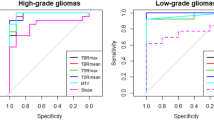

Table 2, on the left side, showed univariable logistic regression results. Four parameters (CBF ASL, nCBF ASL, rCBV DSC, and PET SUVmax) were associated with tumor recurrence from post-treatment changes in patients with glioma (Figs. 2, 3)

Table 2, on the right side, reported the results of the multivariable logistic regression. Only nCBF ASL (p = 0.008) was associated with tumor recurrence from post-treatment changes in patients with glioma with OR = 22.85, CI95%: (2.28–228.77) (Figs. 4, 5). Particularly, patients who showed an increase in this parameter had a risk of recurrence of approximately 23 times compared to subjects who did not experience it.

Our results have highlighted that when the diagnostic techniques were individually assessed through a univariable analysis, three of them showed association in assessing recurrence compared to post-treatment changes in glioma: ASL-PWI (both the absolute and the normalized CBF), DSC-PWI, and 18F-DOPA PET/CT. On the other hand DCE-PWI did not show statistically detectable results.

Anyway, when the examined parameters were assessed through a multivariate analysis, the only statistically detectable parameter was the nCBF ASL, with a 23 times higher risk of disease recurrence in case of elevated nCBF values.

ASL superior performance to the other two PWI sequences is in concordance with the most recent literature.

Berteaux et al. analyzed the role of the hybrid PET/MRI scanners using 18F-DOPA in treated glioma [45], showing how ASL sequences may help mitigate the lower specificity of 18F-DOPA PET in hemorrhagic lesions with macrophage activation with an AUC curve of 0.93 in the combined ASL/PET analysis, which is very similar to our ASL nCBF AUC curve (0.926) and superior to our PET SUVmax AUC curve (0.882) [45].